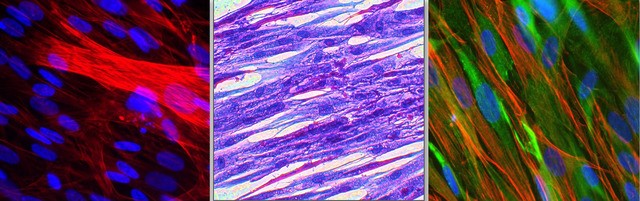

Гладкие и скелетные мышечные клетки